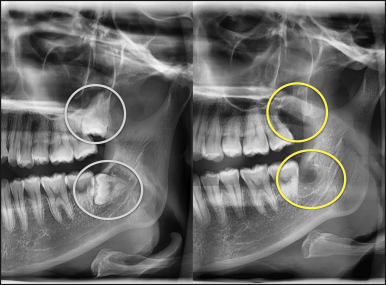

오른쪽 사랑니 안전하게 발치 완료 (좌측) - 왼쪽도 안전하게 발치 완료 (우측)

모든 사랑니 발치를 안전하게 완료하였습니다.